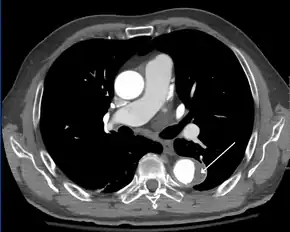

Computed tomography

Computed tomography angiography is a fast, noninvasive test that gives an accurate three-dimensional view of the aorta. These images are produced by taking rapid, thin-cut slices of the chest and abdomen, and combining them in the computer to create cross-sectional slices. To delineate the aorta to the accuracy necessary to make the proper diagnosis, an iodinated contrast material is injected into a peripheral vein. Contrast is injected and the scan performed using a bolus tracking method. This type of scan is timed to an injection to capture the contrast as it enters the aorta. The scan then follows the contrast as it flows through the vessel. It has a sensitivity of 96 to 100% and a specificity of 96 to 100%. Disadvantages include the need for iodinated contrast material and the inability to diagnose the site of the intimal tear.

Aortic dissection

CT with contrast demonstrating aneurysmal dilation and a dissection of the ascending aorta (type A Stanford)